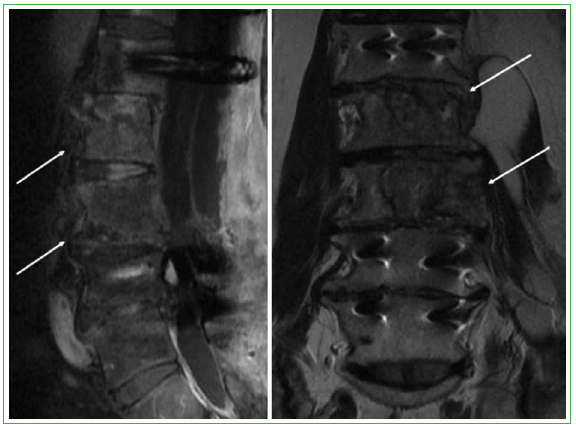

Es operado nuevamente en agosto de 2003 por un quiste hidatídico abdominal. Las molestias y el dolor neuropático en el muslo izquierdo persisten. Durante la cirugía, se detecta un quiste de, al menos, 20 cm de diámetro mayor, que se drena y se reseca en bloque. Se envía una muestra a anatomía patológica y el informe indica quiste hidatídico. En el posoperatorio, se inicia tratamiento con albendazol 400 mg, cada 12 h, en 8 ciclos de 28 días, con períodos de 15 días de descanso entre ellos. En 2008, se detectan quistes retroperitoneales múltiples y un quiste hidatídico del psoas. Persiste el dolor de tipo neuropático, invalidante, y el paciente necesita bastones para deambular. Además, tiene incontinencia vesical y anal, y disfunción eréctil. La resonancia magnética muestra compromiso vertebral de L2-L3, con imágenes quísticas paravertebrales izquierdas sugerentes de hidatidosis asociada a una estenosis raquídea por espondiloartrosis de L3-S1, además de compromiso hidatídico intrarraquídeo, lo que explica la sintomatología neurológica (Figura 1).

Figura 1.

Tomografía computarizada de abdomen y pelvis. A. Corte transversal. Masa lobulada intrapelviana en relación con el psoas ilíaco izquierdo, de aproximadamente 14 cm de largo. B. Corte coronal. Masa lobulada en relación con L1-L2 y L3 izquierda. (Año 2008).